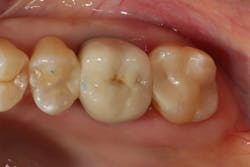

The restorative composite (GrandioSO, Voco) is placed in two separate increments. Each increment is light-cured for 20–30 seconds. An anatomically designed diamond bur (Occlusinator, Strauss) is used to create the initial anatomic form and occlusion. This is then polished to a high shine using a series of composite polishers (Dimanto, Voco).

Using a composite with excellent physical characteristics and careful attention to technique should enable the restoration to provide years of service to the patient (figure 8).